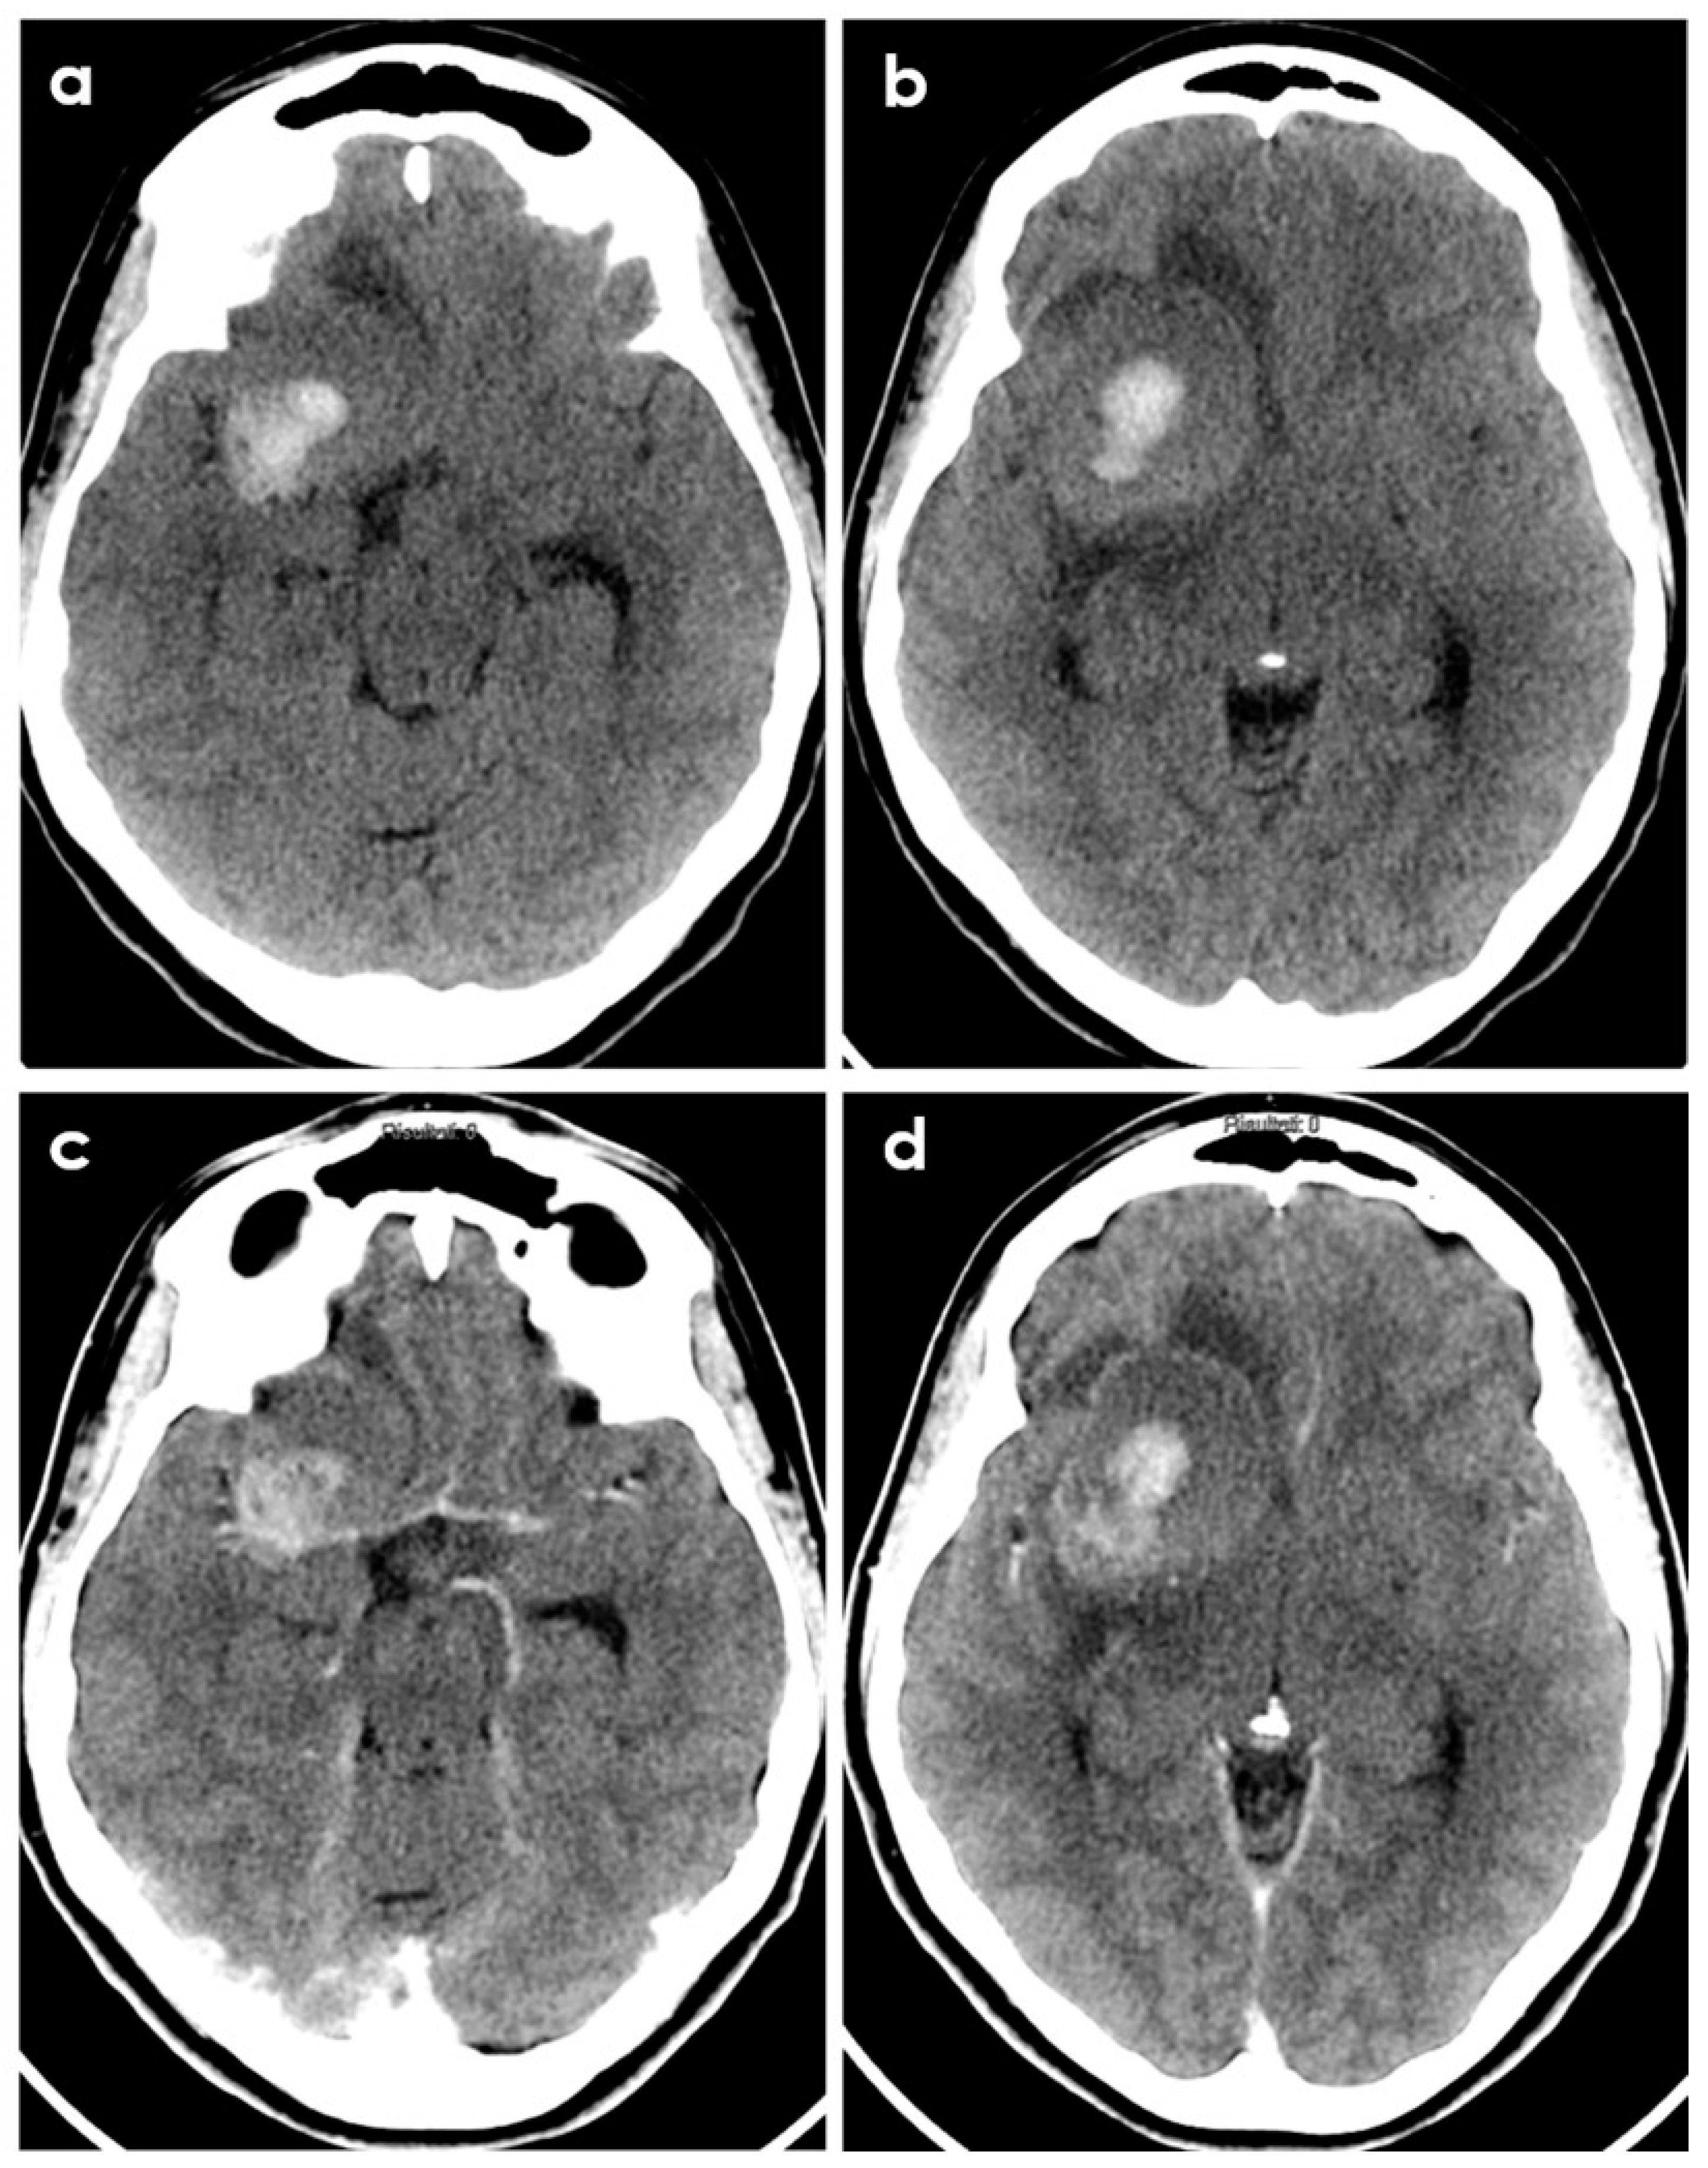

Sometimes PACNS-related ICH may not manifest with a hyperacute appearance on neuroimaging, as shown in Figure 2 and Figure 3.

Figure 2.

Brain CT of a young patient with biopsy-proven PACNS and ICH at presentation. The patient had a history of headache lasting 6 months before imaging. Panels (a,b) show the non-contrast CT appearance of a large rounded parenchymal hematoma with the different densities of the blood degradation products, surrounded by a hypodense rim of edema. Panels (c,d) show the corresponding post-contrast slices highlighting the displacement of the right MCA by the hematoma and the peripheral contrast enhancement of the lesion.